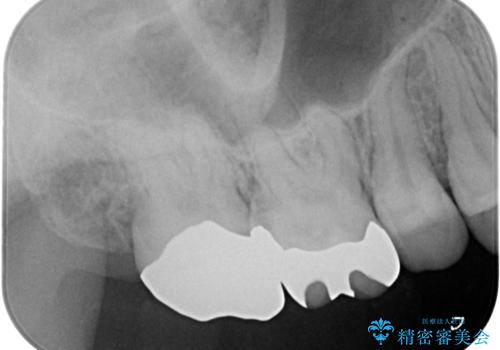

奥歯の虫歯の治療

- 奥歯が虫歯になっていたため治療しました。

手前側の歯は前から見えるため、セラミックの詰め物で治療しました。

奥は高さを取るのが難しかったため薄く作れる金属(ゴールド)で治療しています。

- 合計 26.4万円(内訳:右上7 PGAクラウン 11万円(旧料金)、右上6PGAインレー 7.7万円(旧料金)、右上5 emaxインレー 7.7万円)費用は治療当時の料金となります